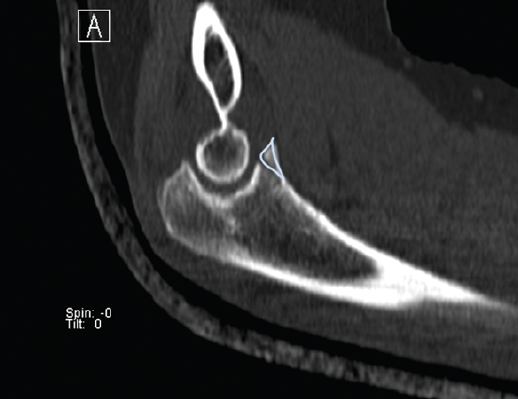

Presentamos el caso de una mujer de 46 años, diestra, sin patología crónica y que trabaja como auxiliar en una residencia geriátrica. Durante su jornada laboral sufre una caída casual presentando dolor y limitación funcional en su codo izquierdo. No presenta deformidades externas en el codo, ni lesiones vasculonerviosas. En el estudio radiológico, se sospecha una fractura de la punta de la apófisis coronoides del codo izquierdo, que correspondería, según la clasificación de Regan y Morrey, al tipo 1 (Figuras 1 y 2). Se comprueba que el codo es estable y se coloca una férula braquial, a la espera de realizar una tomografía computarizada (TC), que confirma la lesión. En la TC podemos visualizar mejor la morfología de la fractura de coronoides tanto en los cortes sagitales (Figura 3), como en los axiales (Figura 4).

Figura 3. Corte sagital de tomografía computarizada, realizado a los 10 días de la lesión. Vemos enmarcada la línea de fractura al nivel de la punta de la apófisis coronoides.